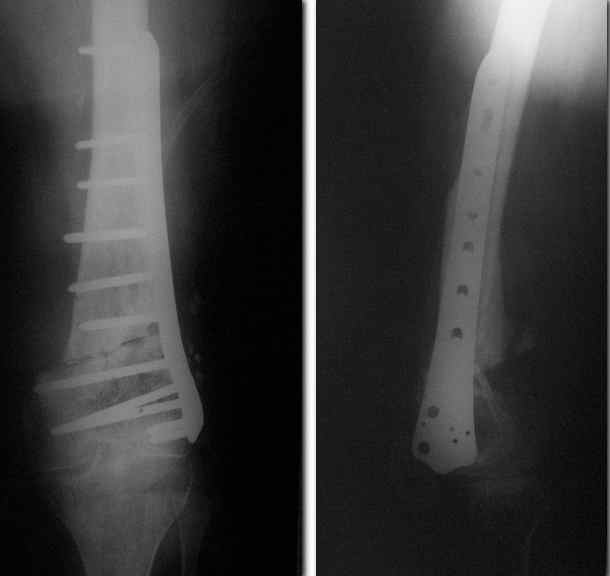

Re: Ложный сустав

Сергей 06 Август 2010, 17:32

Спасибо. Прооперировали во вторник.

Отправитель: Alexander Chelnokov 07 Август 2010, 21:37

Выглядит красиво. А движения в колене какие были на столе?

Отправитель: Сергей 11 Август 2010, 20:37

Была контрактура и спаянный с суставной поверхностью надколенник. Сделали до синтеза редрессацию. Достигли почти полного объема движений.